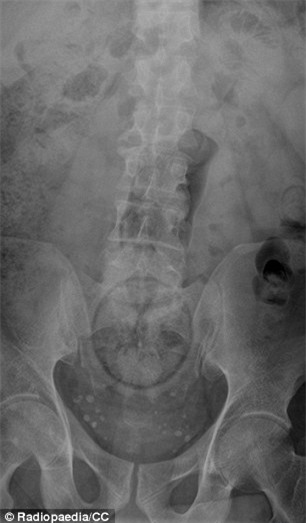

Thật khó tin là nguyên một quả cam có thể chui xuống đến tận trực tràng của bệnh nhân này.